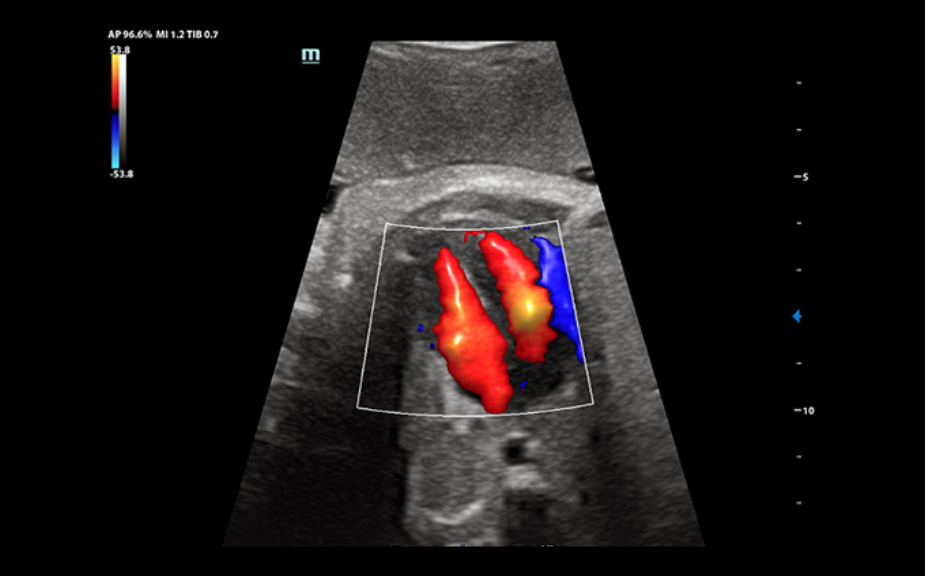

ImГЎgenes ClГӯnicas